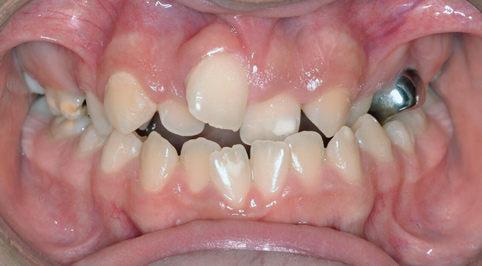

Although the face is a 3-dimensional structure, craniofacial growth modification is a topic that may be stratified by reviewing the transverse, vertical, and anterior-posterior dimensions. A transverse growth inadequacy is often illustrated in the form of a posterior (and often anterior) crossbite.21 The most common cause of this inadequacy is an underdeveloped maxilla, or, alternatively, an overdeveloped mandible; oftentimes a combination of these characteristics is the source of the problem. One example is a patient who has had cleft lip/palate repair, which may lead to craniofacial growth restriction in all dimensions (Figure 6 and Figure 7). When considering the transverse dimension, the most common treatment for a posterior crossbite is RPE therapy.21 In mild cases, archwire or dental expansion may suffice.

Fig 6. Patient with cleft palate treatment history and underdeveloped craniofacial growth, facial view (Fig 6) and occlusal view (Fig 7).

Figure 6

Fig 7. Patient with cleft palate treatment history and underdeveloped craniofacial growth, facial view (Fig 6) and occlusal view (Fig 7).

Figure 7